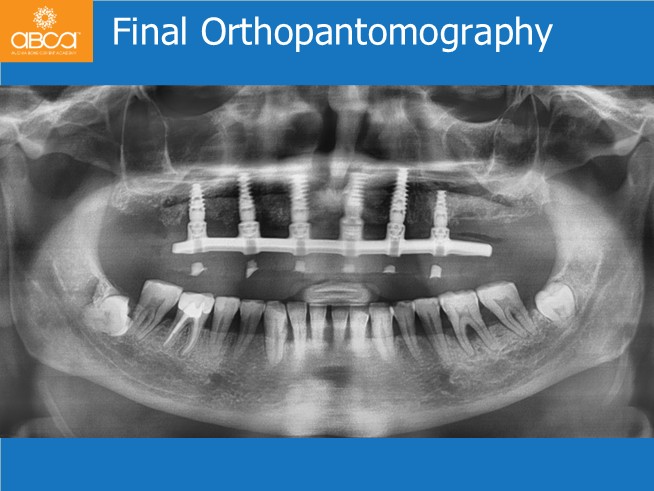

Treatment includes the extraction of all the remaining teeth, careful cleaning of all the sockets. Without opening a flap, placement of 3 implants to achieve an All-on-6, socket grafting and immediate load. Placement of the final Nobel Procera hybrid prothesis after 6 months.